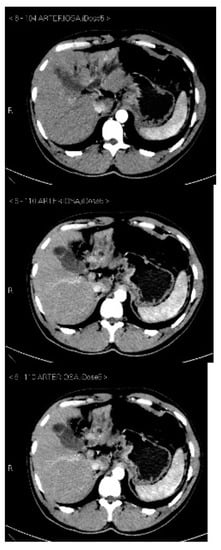

Subsequently, an upper-abdomen Computed Tomography (CT) scan and liver Magnetic Resonance Imaging (MRI) were performed (Figure 1, Figure 2, Figure 3, Figure 4, Figure 5, Figure 6 and Figure 7).

Figure 1.

CT arterial phase.

Figure 6.

MRI arterial, portal, and HPB phases.

A mass of 1.8 cm was detected within the biliary branch for the third hepatic segment, characterized by nodular impregnation in the arterial phase and irregular and partial washout in the portal venous phase. These findings were compatible with a heterologous lesion, although it was not possible to perform a diagnosis among HCC, intrahepatic CCA or other pathological lesions.

HCC typically has an increased arterial blood supply, so it usually shows hyperattenuation in the arterial phase and hypoattenuation in the portal venous phase, compared to the hepatic parenchyma.

Most HBDTTs should show the same enhancement pattern. However, some HCCs can show iso- or hypoattenuation in the arterial phase, with the enhancement in the arterial phase inversely correlated with the degree of blood clots and necrosis. So, hypoattenuation in the portal venous phase seems to be the most important imaging feature to distinguish HCC with BDTT from perihilar CCA [17].